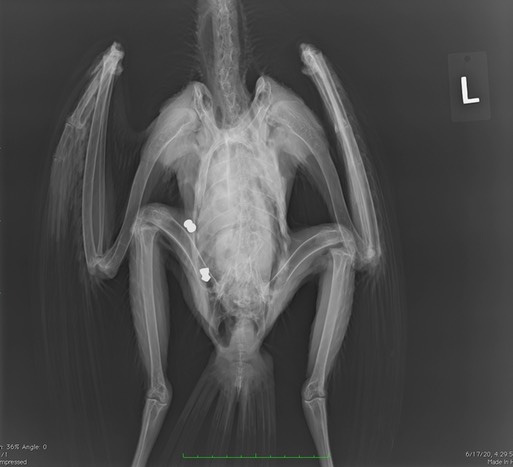

Sadly, the first radiograph taken with the new machine was of gunshot Red-tailed Hawk 20-298. Volunteers Mark and Shelly captured the hawk in Yakima. It died before reaching Pendleton. There was a suspicious looking wound in the abdominal area. The radiograph confirmed the hawk had been shot twice.